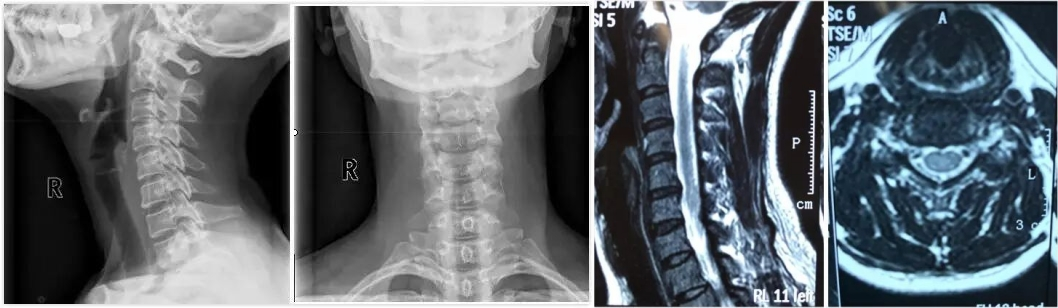

年近五十的谢女士,被反复颈部酸痛困扰了四年之久,近两个月更是加重到出现右侧上肢麻木。长时间低头工作后,颈项僵硬、前额胀痛、头晕目眩频频发作,连夜间安睡都成了奢望。经检查,她被明确诊断为神经根型颈椎病,颈椎生理曲度变直,伴有侧弯和椎间盘突出。

面对复杂的病情,在市中医医院定期坐诊的南京中医药大学针灸临床教研室专家李开平并未局限于常规思路,运用了一套严谨的“辨位选点”方法。通过细致的姿势和功能检查,结合影像学资料,准确找到了因劳损、失衡而变得紧张、粘连的筋膜、肌肉关键部位——“靶弓弦”。

治疗过程如同一次次精密的“导航松解”。首次治疗,针对颈后大区域进行“大T形”松解,术后谢女士便感到颈部僵硬缓解,头晕、头胀减轻。第二次,松解范围更聚焦,处理了肩背部菱形肌的压痛点,效果叠加:僵硬感明显缓解,疼痛和头晕次数减少,睡眠开始改善。第三次治疗,在颈项线、棘突、关节突及肩胛周围等多点进行立体松解后,效果显著推进:酸痛僵硬大幅减轻,头晕消失,睡眠质量跃升。最后一次治疗,重点处理了颈椎横突周边及肩部相关肌群附着点,配合医院指导的颈部拉伸、抗阻训练及蛙泳等康复运动巩固疗效,增强颈肩肌群力量与协调性,折磨谢女士多年的颈项僵硬酸痛基本消失,不再头晕、头胀,睡眠也焕然一新。

李开平介绍,治疗的关键在于“辨位选点”的完整逻辑:从准确评估出发,精准定位病变的力学平衡失调点(靶弓弦),进而理解整个颈肩部的立体病理网络,最后进行有的放矢的松解治疗,必要时动态评估调整。这种思路确保了治疗既能直击要害,又兼顾整体平衡。